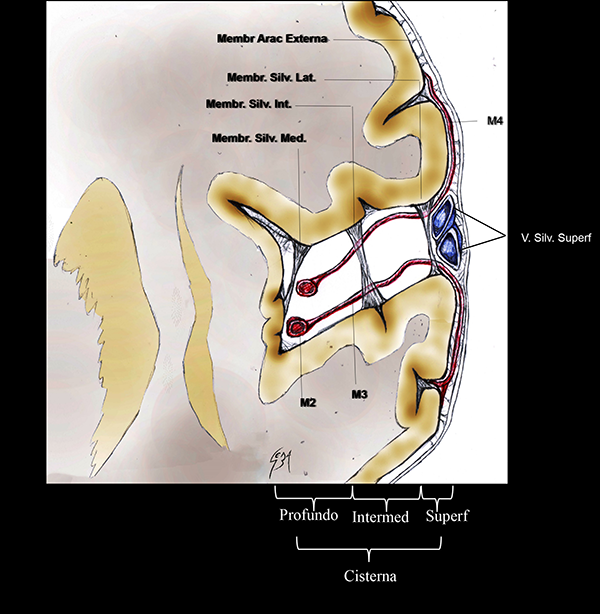

Figura 2: Dibujo esquemático de una vista coronal de la FS izquierda con sus membranas aracnoideas. La cisterna silviana se sitúa entre la membrana aracnoidea externa y la piamadre. Su parte lateral tiene 3 membranas silvianas internas que dividen el espacio subaracnoideo: lateral, intermedia y medial. Membr Arac: membrana aracnoidea; Membr Silv: membrana silviana. V. Silv. Superf: venas silvianas superficiales. Intermed: intermedio.

En un completo estudio de Inoue et al.,28 se describe a la cisterna silviana limitada por la membrana aracnoidea externa y la piamadre. Numerosas trabéculas y membranas internas cruzan a lo largo de ella, dividiendo al espacio subaracnoideo en compartimientos más pequeños (Figura 2).

Las membranas aracnoideas intrasilvianas de la cara lateral de la FS son esquematizadas en 3, acorde a la literatura:28 la membrana lateral, intermedia y medial. La membrana silviana lateral es la más superficial. El trayecto de las venas silvianas superficiales y el segmento M4 de la ACM se ubica entre esta membrana y la membrana aracnoidea externa. Se adhiere a los márgenes laterales de los opérculos frontoparietotemporales. La membrana silviana intermedia se relaciona con la porción medial de los opérculos y se localiza lateral al segmento M2. La membrana silviana medial es la más profunda de todas y se localiza medial a M2. Está adherida al margen más profundo del opérculo frontoparietal y la corteza insular (Figura 2).28

La membrana aracnoidea silviana intermedia divide arbitrariamente al aspecto lateral de la cisterna silviana en dos compartimientos.28 Medial a esta membrana, se ubica la hendidura insular lateral. Las venas silvianas profundas y el segmento M2 se localizan en este compartimiento. Lateral a la membrana silviana intermedia, se encuentra el compartimiento opercular lateral (Figura 2).